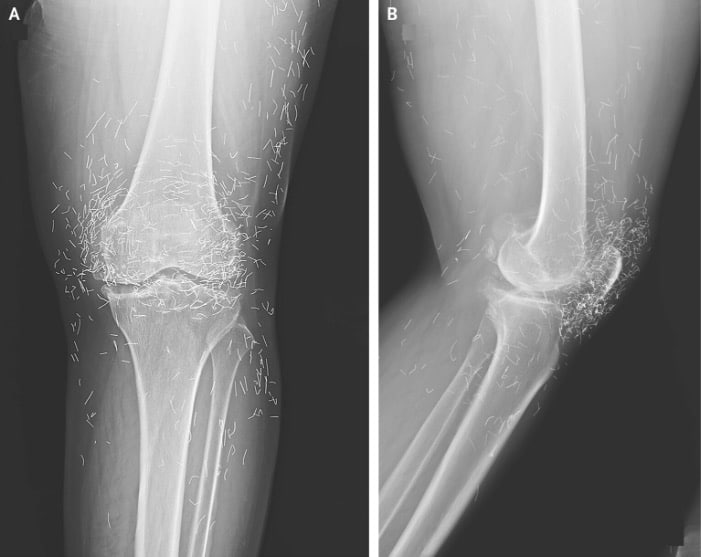

Years later, when doctors took X-rays to evaluate her knee condition, they weren’t prepared for what appeared on the images. Her knees were filled with dozens of bright, metallic flecks — tiny needles embedded deep within the joint area.

The findings were later documented in a case published by the New England Journal of Medicine.

Beyond inflammation, the needles created another problem: imaging complications. Metal objects can obscure parts of the anatomy on X-rays, making it harder for doctors to clearly assess joint damage or disease progression.

Even more concerning, the presence of metal inside the body can make certain scans dangerous. MRI machines rely on powerful magnetic fields, and embedded needles may shift during scanning, potentially damaging blood vessels or surrounding tissue. In short, future diagnostic options for this patient became limited.